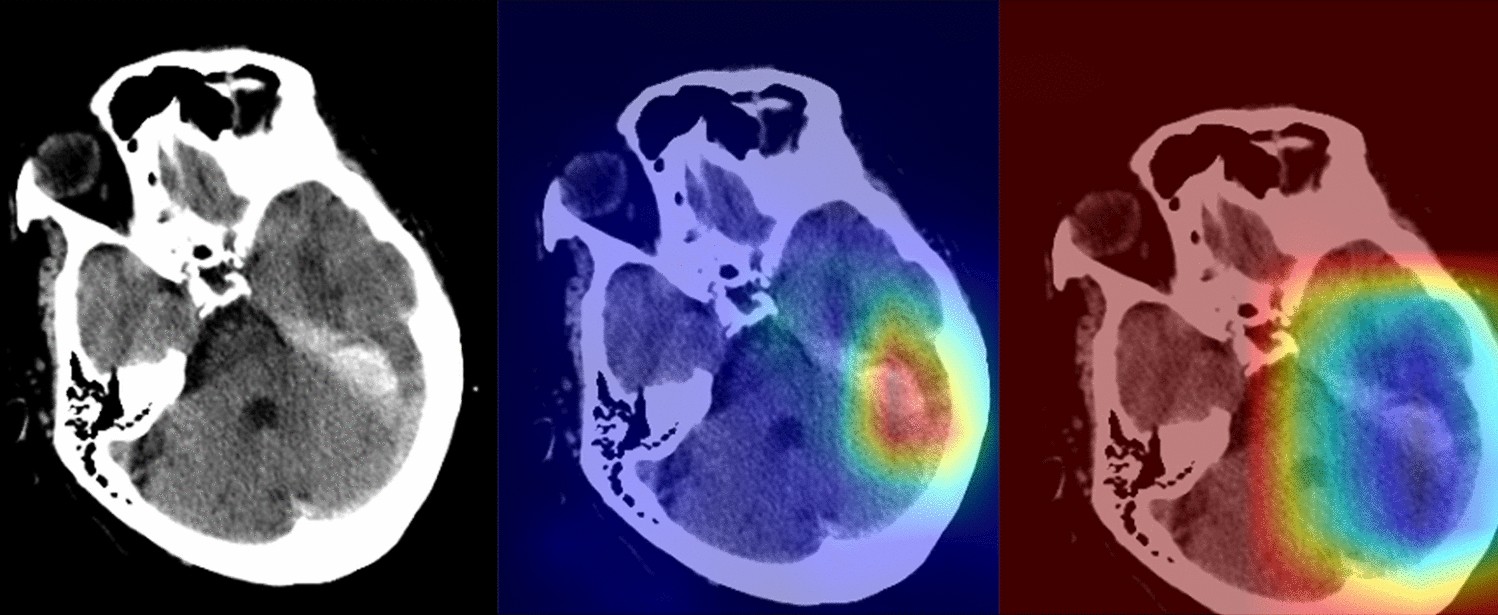

Figure 4

A 71-year-old man with a recent history of head trauma (The images were created by the authors using open-source software, Matplotlib v3.5, Python v3). Non-contrast head CT scan shows a subdural hematoma along the left tentorium cerebelli (right). NormGrad (middle) method generates finer saliency maps than Grad-CAM (left), highlighting the subdural hematoma. The average quality scores were 3.8 points and 1.8 points for the NormGrad and Grad-CAM, respectively. Please note that the observers evaluated saliency maps with the same color spectrum, and the current color maps are adjusted for representative purposes.